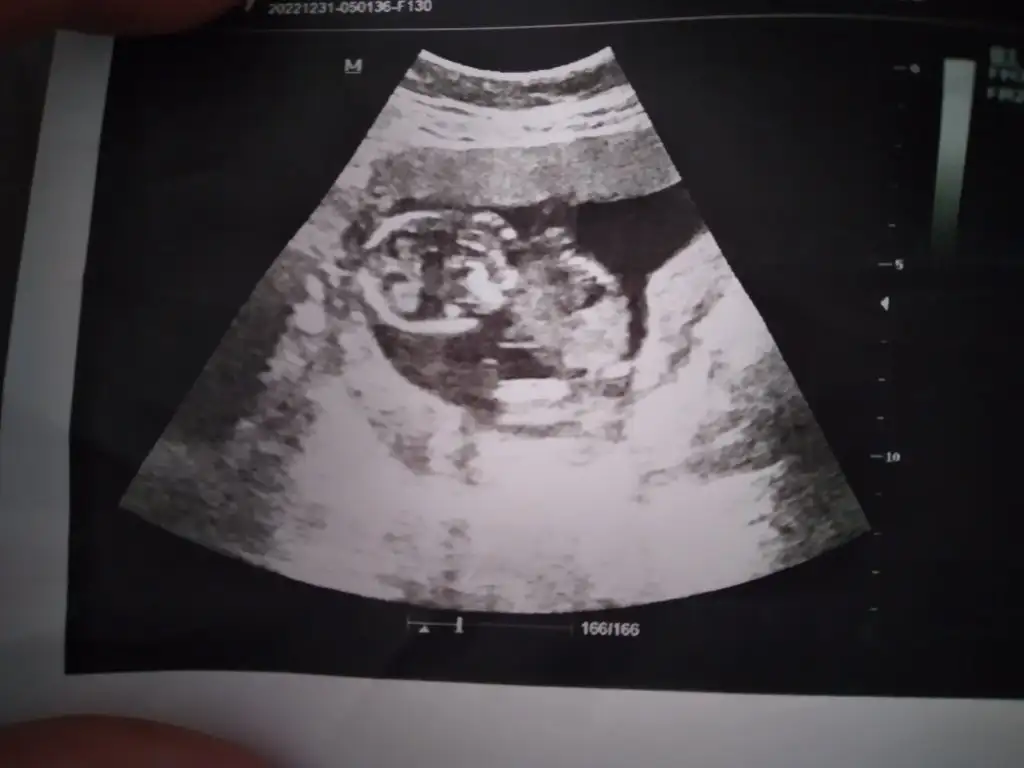

İcimden kız geçti saglikla doğsunMerhaba arkadaşlar bugün 18+3 haftalığız

En son gittiğimde 16+5 ti cinsiyetini göstermedi siz tahmin yapabilir misiniz acaba ? Hayırlısı ne ise o olsunEki Görüntüle 3199761